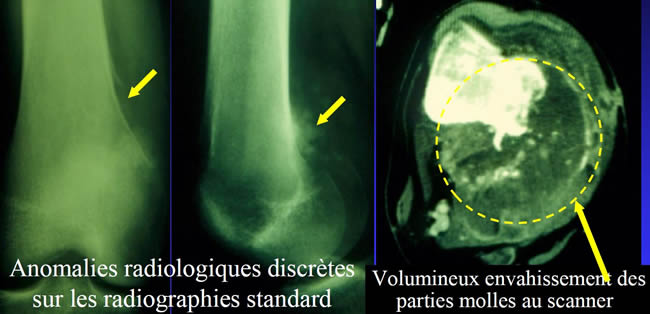

Aspect trompeur évoquant une tumeur à cellules géantes

- Radiographies : discrète ostéolyse évoquant plutôt une tumeur bénigne à cellules géantes.

- Jeune femme de 25 ans souffrant de son genou selon un rythme mécanique depuis 3 mois.

C'est dans ces cas difficiles que le scanner prend tout son intérêt.

L'atteinte des partie molles découverte au scanner fait craindre la malignité.